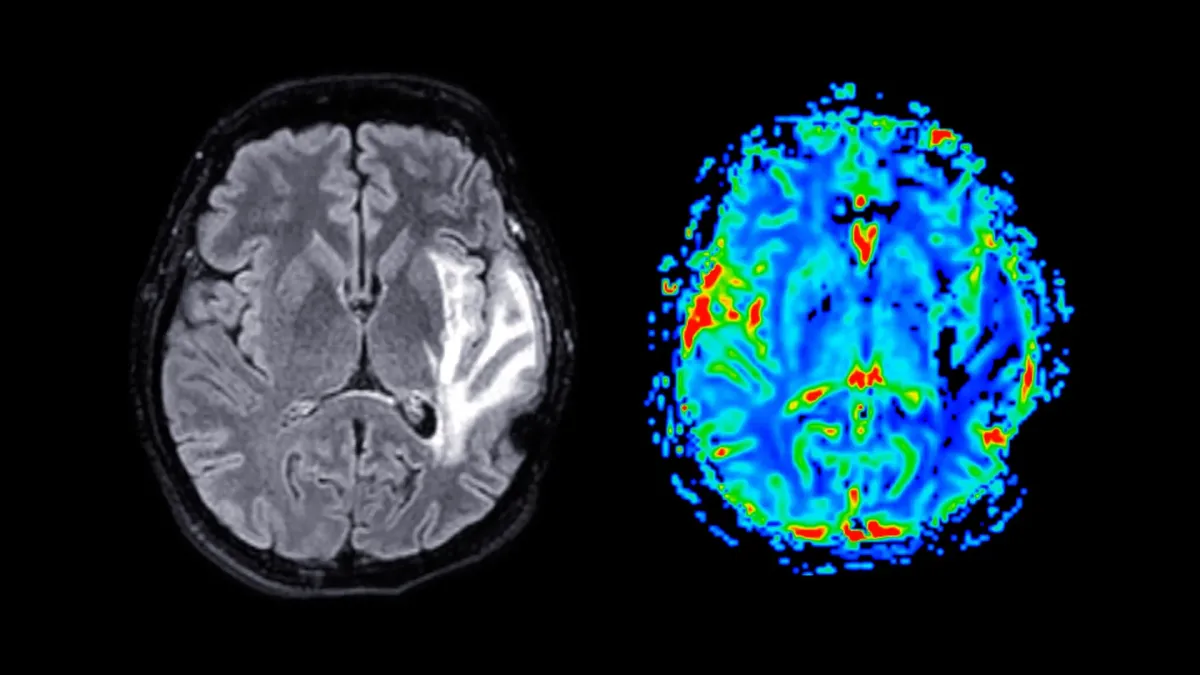

A new genetic study suggests that obesity and high blood pressure don't just increase dementia risk — they may directly cause it. Researchers analyzing data from Denmark and the U.K. found strong evidence that carrying extra weight damages brain health over time, particularly when it leads to elevated blood pressure. Much of this damage appears to happen through vascular injury in the brain, which disrupts blood flow and cognitive function.

The analysis revealed something important: much of the dementia risk linked to obesity appears to flow through high blood pressure. In other words, weight gain damages the brain partly by raising blood pressure, which then damages the blood vessels that feed brain cells. This finding suggests that interventions targeting both conditions — not just one — could lower dementia risk later in life.